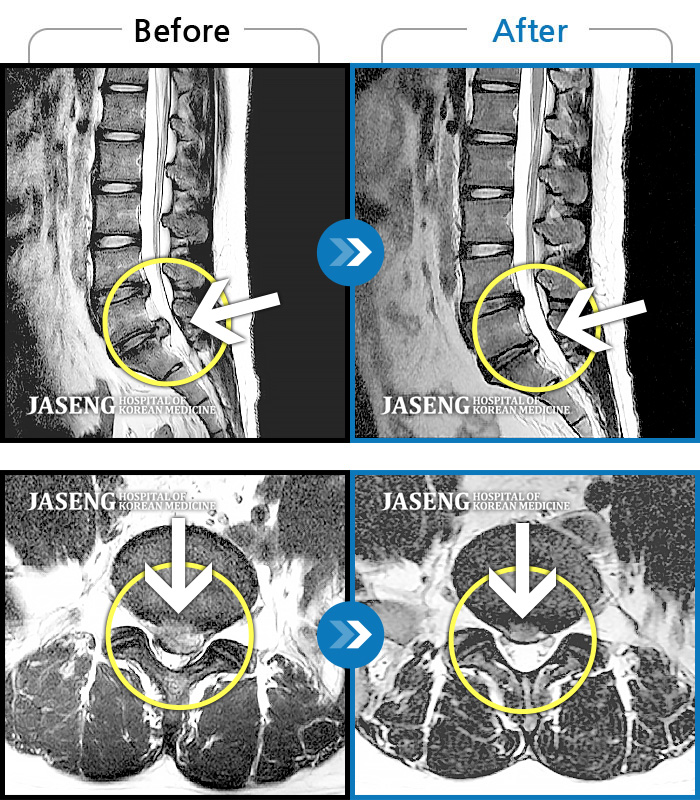

• 허리디스크